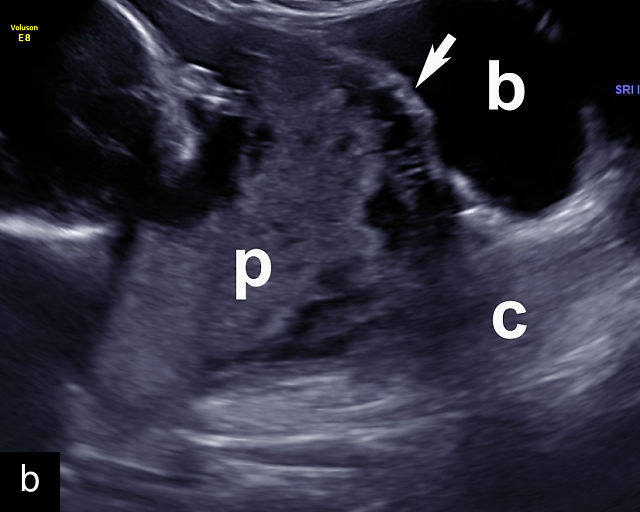

6

Placenta accreta spectrum. (a,b) Sagittal transabdominal grayscale ultrasound of the lower uterus and cervix demonstrating placenta previa accreta, with the placenta (p) containing prominent irregular hypoechoic lacunae. There is absence of the myometrium at the bladder (b) interface (arrows) c, cervix. (c) Sagittal transabdominal color Doppler ultrasound of the lower uterus and cervix demonstrating placenta previa accreta, with increased vascularity of the lower uterus and the myometrial bladder interface. (d) Transvaginal ultrasound of placenta previa accreta showing multiple lacunae involving the cervix with no clear demarcation between the placenta and the cervix. (e) Transvaginal ultrasound of placenta previa accreta showing multiple large irregular lacunae involving the cervix with no clear demarcation between the placenta (p) and the cervix. The placenta has a ‘moth-eaten’ appearance. There is loss of myometrium (arrows). (f) Transvaginal ultrasound of placenta previa accreta without and with color flow Doppler showing multiple large irregular lacunae. The placenta has a ‘moth-eaten’ appearance. There is hypervascularity of the myometrial interface. (g) Transvaginal ultrasound of placenta previa accreta showing multiple lacunae involving the cervix with no clear demarcation between the placenta and the cervix. (h) Transvaginal ultrasound of placenta previa accreta with color flow Doppler showing hypervascularity of the myometrial interface and irregularity of the bladder wall. b, bladder; p, placenta. (i) Transabdominal grayscale ultrasound of cesarean scar pregnancy. The uterine fundus (f) is empty (arrowhead). The gestational sac (arrow) is located in the lower uterus, anterior to the uterine canal, and lies above the cervix (c). b, bladder. (j) Transvaginal grayscale ultrasound image of cesarean scar pregnancy showing the empty fundus (f) and the normal cervix (c). The gestational sac lies below the fundus, above the cervix and anterior to the uterine cavity. (k) Transvaginal grayscale ultrasound image of cesarean scar pregnancy showing the empty cavity (arrowheads) of the uterine fundus (f), and the normal cervix (c). The gestational sac lies below the fundus, above the cervix and anterior to the uterine cavity (arrow).

Several characteristic sonographic findings are associated with PAS.90,95,96,97 These include placental lacunae, which appear as hypoechoic, irregular spaces within the placenta with high-velocity turbulent flow on color Doppler.16,50 Other features include obliteration of the retroplacental clear space, thinning of the myometrium in the lower uterine segment, irregularity and hypervascularity of the myometrial–bladder interface, and placental bulging into the bladder (Figure 6a–h).90,96,98,99